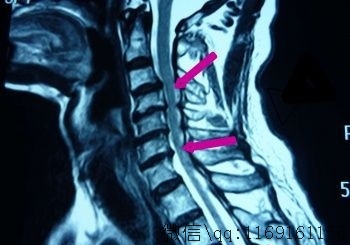

在诊断上,可用X线、脊髓造影等手段,必要时可用CT、磁共振成像等仪器。X线片上一般可见颈椎生理前凸减小或消失,动力性侧位片可显示椎节梯形变,以第34颈椎节最为多见,上、下椎体位移超过2毫米的,具有临床意义;椎节前、后位移伴有椎节前方狭窄、后方增宽的,则更具有诊断意义。CT、磁共振成像检查可直接获得清晰的影像,提高诊断的准确率,其中脊髓造影加CT检查对诊断侧方型椎间盘突出症的价值大于磁共振成像检查。